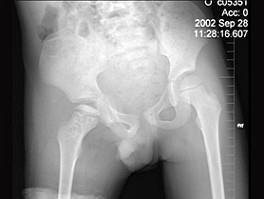

问题 7岁男孩,发现跛行半年伴疼痛,来科行双髋关节正位片,如图所示,最佳的诊断是 ( )

选项 A、克丁病 B、右髋关节肿瘤 C、右股骨头骨软骨炎 D、右侧扁平髋 E、右髋关节结核

答案 C